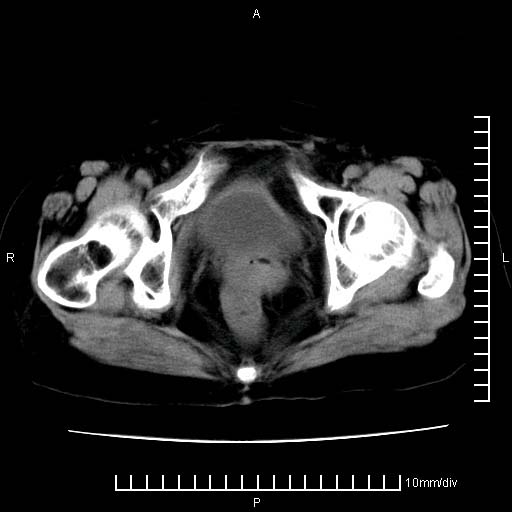

下腹疼痛2月,加重并呕吐2天,下腹压痛,反跳痛。白细胞1万2.

下腹至盆腔较大包块,与邻近肠管关系密切,下腹疼痛2月,加重并呕吐2天,下腹压痛,反跳痛。白细胞1万2.

由于没有做肠道准备很难分清是哪根肠管,但看位置考虑为升结肠回盲部的问题,我首先考虑化脓性阑尾炎,不除外结肠癌合并感染化脓。建议做增强进一步明确。

补充:道格拉斯腔内有积液,且密度较高,显然提示有感染。

考虑右侧卵巢囊肿伴感染可能性大。

附件实性肿块有坏死 考虑卵巢癌

盆腔脓肿伴盆腔积液

来源于附件占位—多考虑:卵巢癌!

不知道大家可要注意下腹腔小肠旁不规则结节状灶,部分钙化,是否要考虑小肠腺癌.盆腔包块可能考虑脓肿.

考虑卵巢恶性肿瘤;盆腔积液。